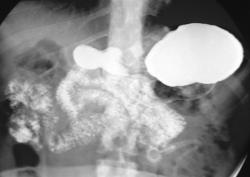

Не, тоже не то. верхние снимки выполнены в положении стоя, последние в положении лёжа. Подсказка есть в самих снимках. Я извиняюсь за качество; у меня флюроскопия записывается в виде цифрового видео, пришлось "ловить стоп-кадры для публикации.

Общая брыжейка-да, наиболее вероятно. Но не это главная причина, по которой я опубликовал данное наблюдение. Инверсии нет; я уже указал что снимки это стоп-кадры с записи флюорографического исследования, поэтому получается зеркальное изображение. В случае инверсии, я конечно бы разместил обзорный снимок. Патология исключительно в желудке, и это наглядно видно. Я понимаю что "играю-немного-не-по-честному", но я сразу указал что это именно загадка. "Подсказка"-это не дренаж; пациентка пришла амбулаторно.

Валентин Львович, дело не в вдавлениях по медиальному краю; и конечно адекватная оценка состояния желудка невозможна без минимума стандартных проекции. Но, вся информация на основании которой можно догадаться о правильном ответе, есть на представленных снимках.

Не, тоже не то. верхние снимки выполнены в положении стоя, последние в положении лёжа. Подсказка есть в самих снимках.

Общая брыжейка-да, наиболее вероятно. Но не это главная причина, по которой я опубликовал данное наблюдение. Инверсии нет; я уже указал что снимки это стоп-кадры с записи флюорографического исследования, поэтому получается зеркальное изображение. В случае инверсии, я конечно бы разместил обзорный снимок.

Патология исключительно в желудке, и это наглядно видно. Я понимаю что "играю-немного-не-по-честному", но я сразу указал что это именно загадка. "Подсказка"-это не дренаж; пациентка пришла амбулаторно.